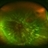

- retinal detachment with retinal defect, proliferative vitreoretinopathy (PVR)

- Wide field fundus photography, Optomap

- Wide field fundus photograph of a 59-year-old male with chronic total RD and PVR, with multiple retinal breaks that developed a few months after LASIK surgery.